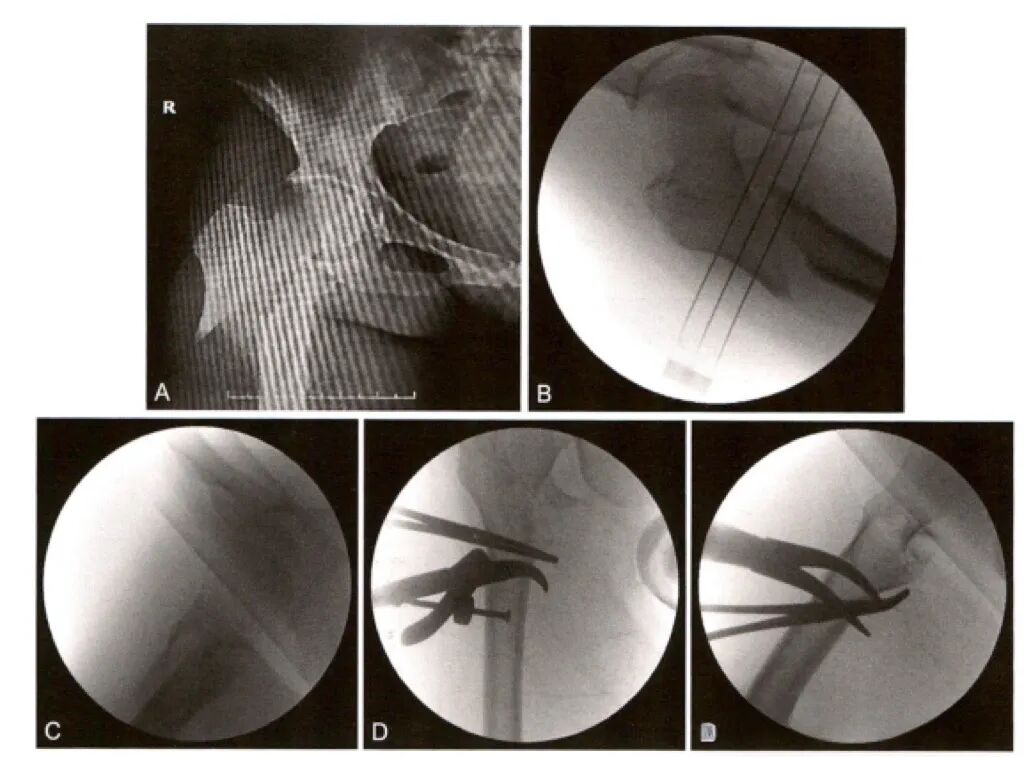

手术复位技术

一、复位技术一(参考解放军总医院创伤骨科手术学)

1.外展屈曲移位骨折:

2.近端屈曲畸形骨折:

可以在前方钻入一枚单皮质 Schanz针,连接T形手柄向远端牵拉,下压近端骨块,进行复位

或者在近端骨块外侧和前方经小切口分别置人两枚顶棒,下压并向内顶推复位

3.近端外展、屈曲骨折:

可以将髓内钉插入骨折近端,利用髓内钉作为摇杆,控制骨折近端进行复位。但该方法难以控制进针点和进针方向,较少使用。

4.远端向内移位骨折:

可以在远端使用骨钩,同时近端配合顶棒进行复位。

二、复位技术二(参考实用髓内针治疗学:王秋银主编2023年)

1.经皮撬拨复位技术和joystick技术(操纵杆技术)

2.经皮钳夹技术及术中外展牵引术

3.经皮钳夹技术及joystick技术